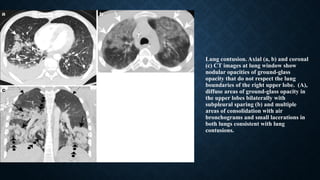

Lung contusion. Axial (a, b) and coronal

(c) CT images at lung window show

nodular opacities of ground-glass

opacity that do not respect the lung

boundaries of the right upper lobe. (A),

diffuse areas of ground-glass opacity in

the upper lobes bilaterally with

subpleural sparing (b) and multiple

areas of consolidation with air

bronchograms and small lacerations in

both lungs consistent with lung

contusions.